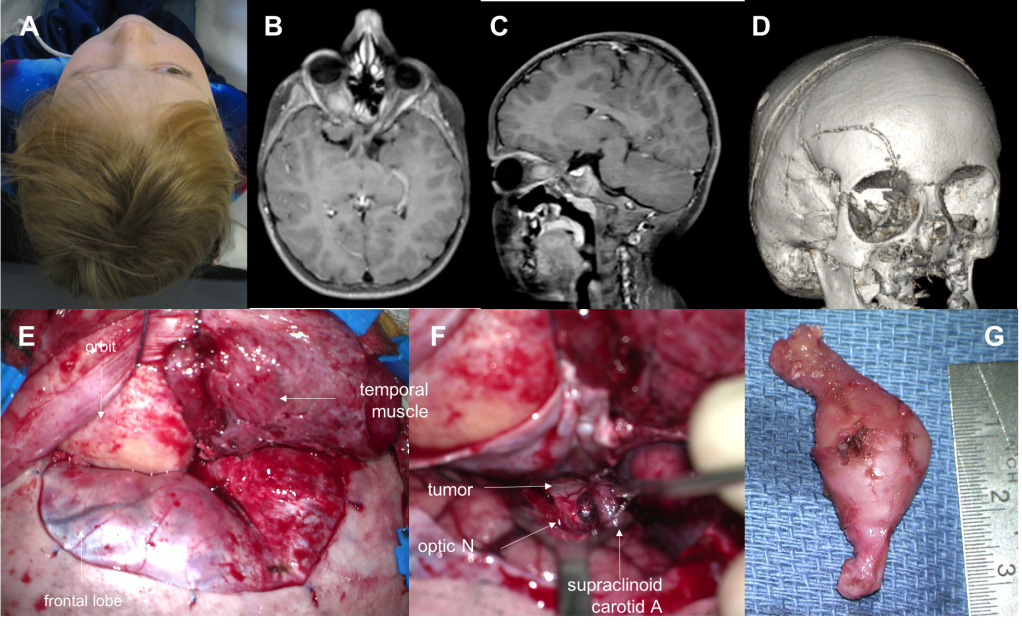

suivant que la tumeur est purement intra-orbitaire ou s’étend en intra-cisternal, on optera pour

- une orbitotomie par abord palpébral avec dépose du rebord orbitaire pour abord purement extra-dural

- une craniotomie avec dépose du rebord et du toît orbitaire pour abord extra- et intra-dural